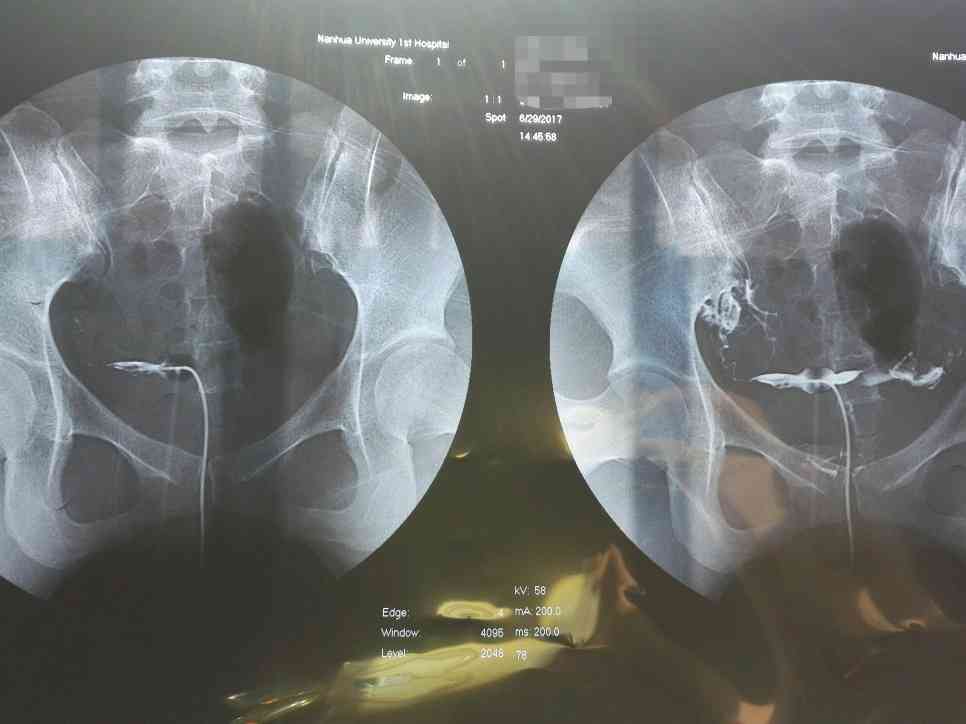

吃了一年中藥,終於鼓起勇氣去造了個影,因為去年造影的疼痛還記憶猶新,沒想到並沒有想象中的痛,而且雙側輸卵管都通暢了。我是被無數醫生判死亡令的那種,去年5月23日,第一次造影結果雙側輸卵管不完全梗阻,雙側傘端粘連梗阻、積水,右側傘端上舉,雙側輸卵管炎,子宮內膜炎。去了好幾家醫院醫生都說必須手術,中醫效果不大,僅一家以學術研究為主的中醫研究所告訴我中醫可以治,因為害怕手術,我最終選擇了中醫治療。拿到片...